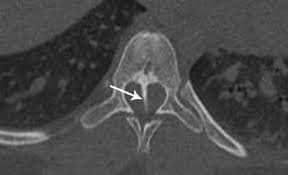

فقد تم اجراء عمليه جراحيه معقدة ونادره لطفل يبلغ من العمراسبوعين يعاني من تشوه خلقي مزدوج من فتق سُحائي وتشوه في العمود الفقري مع وجود نتوء عظمي يتسبب بـ نخاع شوكي منشق (مزدوج (

ولأول مرة في مستشفى الزرقاء الحكومي من قبل الدكتور فراس حداد / استشاري أول جراحة الدماغ والأعصاب، رئيس إختصاص جراحة الدماغ والأعصاب في الخدمات الطبية الملكية سابقاً الذي قام بإجراء العمليه، بمساعدة نخبة مميزة من الكادر الطبي على رأسهم الدكتور رأفت بواعبه مقيم جراحه الدماغ والاعصاب. كما شارك الكادر التمريضي وانجاح العملية وعلى راسهم الممرض مراد الزيود و الممرضة هبه المومني و الممرضة خوله ابوهاني جهودكم مشكوره بالاضافة الى أطباء قسم التخدير اطباء التخدير الدكتور أنس وفنية التخدير إيناس